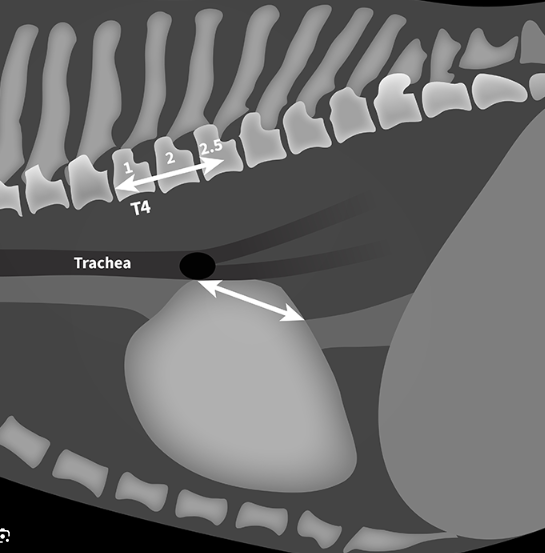

모식도에서 처럼 기관분지부의 아래중심부 끝점에서 대정맥과 심장이 겹쳐지는 부분까지의 거리를 측정하는 방법으로 측정된 길이와 흉추 4번부터 흉추체의 길이를 비교하는 측정방법이다.

cut off는 2.3으로 이보다 크면 심비대를 의미한다.

| 개의 VLAS 정상범위 : 1.8~2.3 |